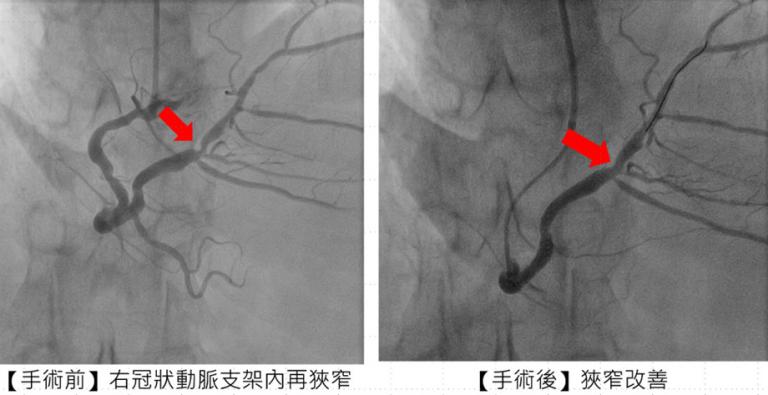

針對張先生的治療過程,市醫副院長兼心臟科專家陳建鈞醫師進一步說明,病人有多次支架再阻塞的病史,加上長途奔波與生活壓力,病情更加複雜。經團隊縝密評估後,決定採用「刀片氣球」及「塗藥氣球」治療,既能打通血管阻塞,也可降低再度狹窄的風險,大幅縮短康復時間。手術全程順利,患者隔日即可出院,術後更能安心規劃生活與健康管理。

▲治療前與治療後,施行「刀片氣球」及「塗藥氣球」治療後,右冠狀動脈支架狹窄改善。(圖/蕭任峰翻攝)